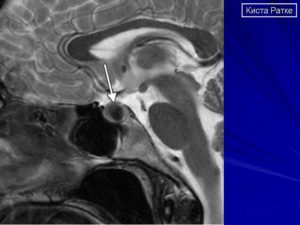

Если предполагается злокачественный характер опухоли, показана консультация онколога. Один из самых информативных методов диагностики – МРТ исследование, которое позволяет дифференцировать кисту, сформировавшуюся в зоне кармана Ратке, от таких патологий, как арахноидальные кисты или аденомы гипофиза (пролактиномы).

На снимке отчетливо видно хорошо отграниченное новообразование кистозной структуры округлой или продолговатой формы иногда с утолщенной стенкой. КТ-томография показывает большую плотность ткани кисты по сравнению с окружающей мозговой тканью.

На снимке МРТ стрелочками указана киста и аденогипофиз, который всегда деформирован кистой, и киста непосредственно к нему прилегает

Плотность содержимого кисты ниже, чем окружающая ткань, если преобладает жидкостный компонент внутри. При усиленном накоплении белков и мукополисахаридов консистенция становится желеобразной. В редких случаях имеется неоднородность сигнала за счет того, что присутствуют включения жиров, распавшейся крови, слущенного слоя эпителия, который выстилает изнутри кисту.

Окружающая ткань гипофиза может выглядеть более плотной, так как отмечается сдавление его клеток. При аденоме, наоборот, соседние области разрежены, так как максимальная гормональная активность наблюдается внутри опухоли.